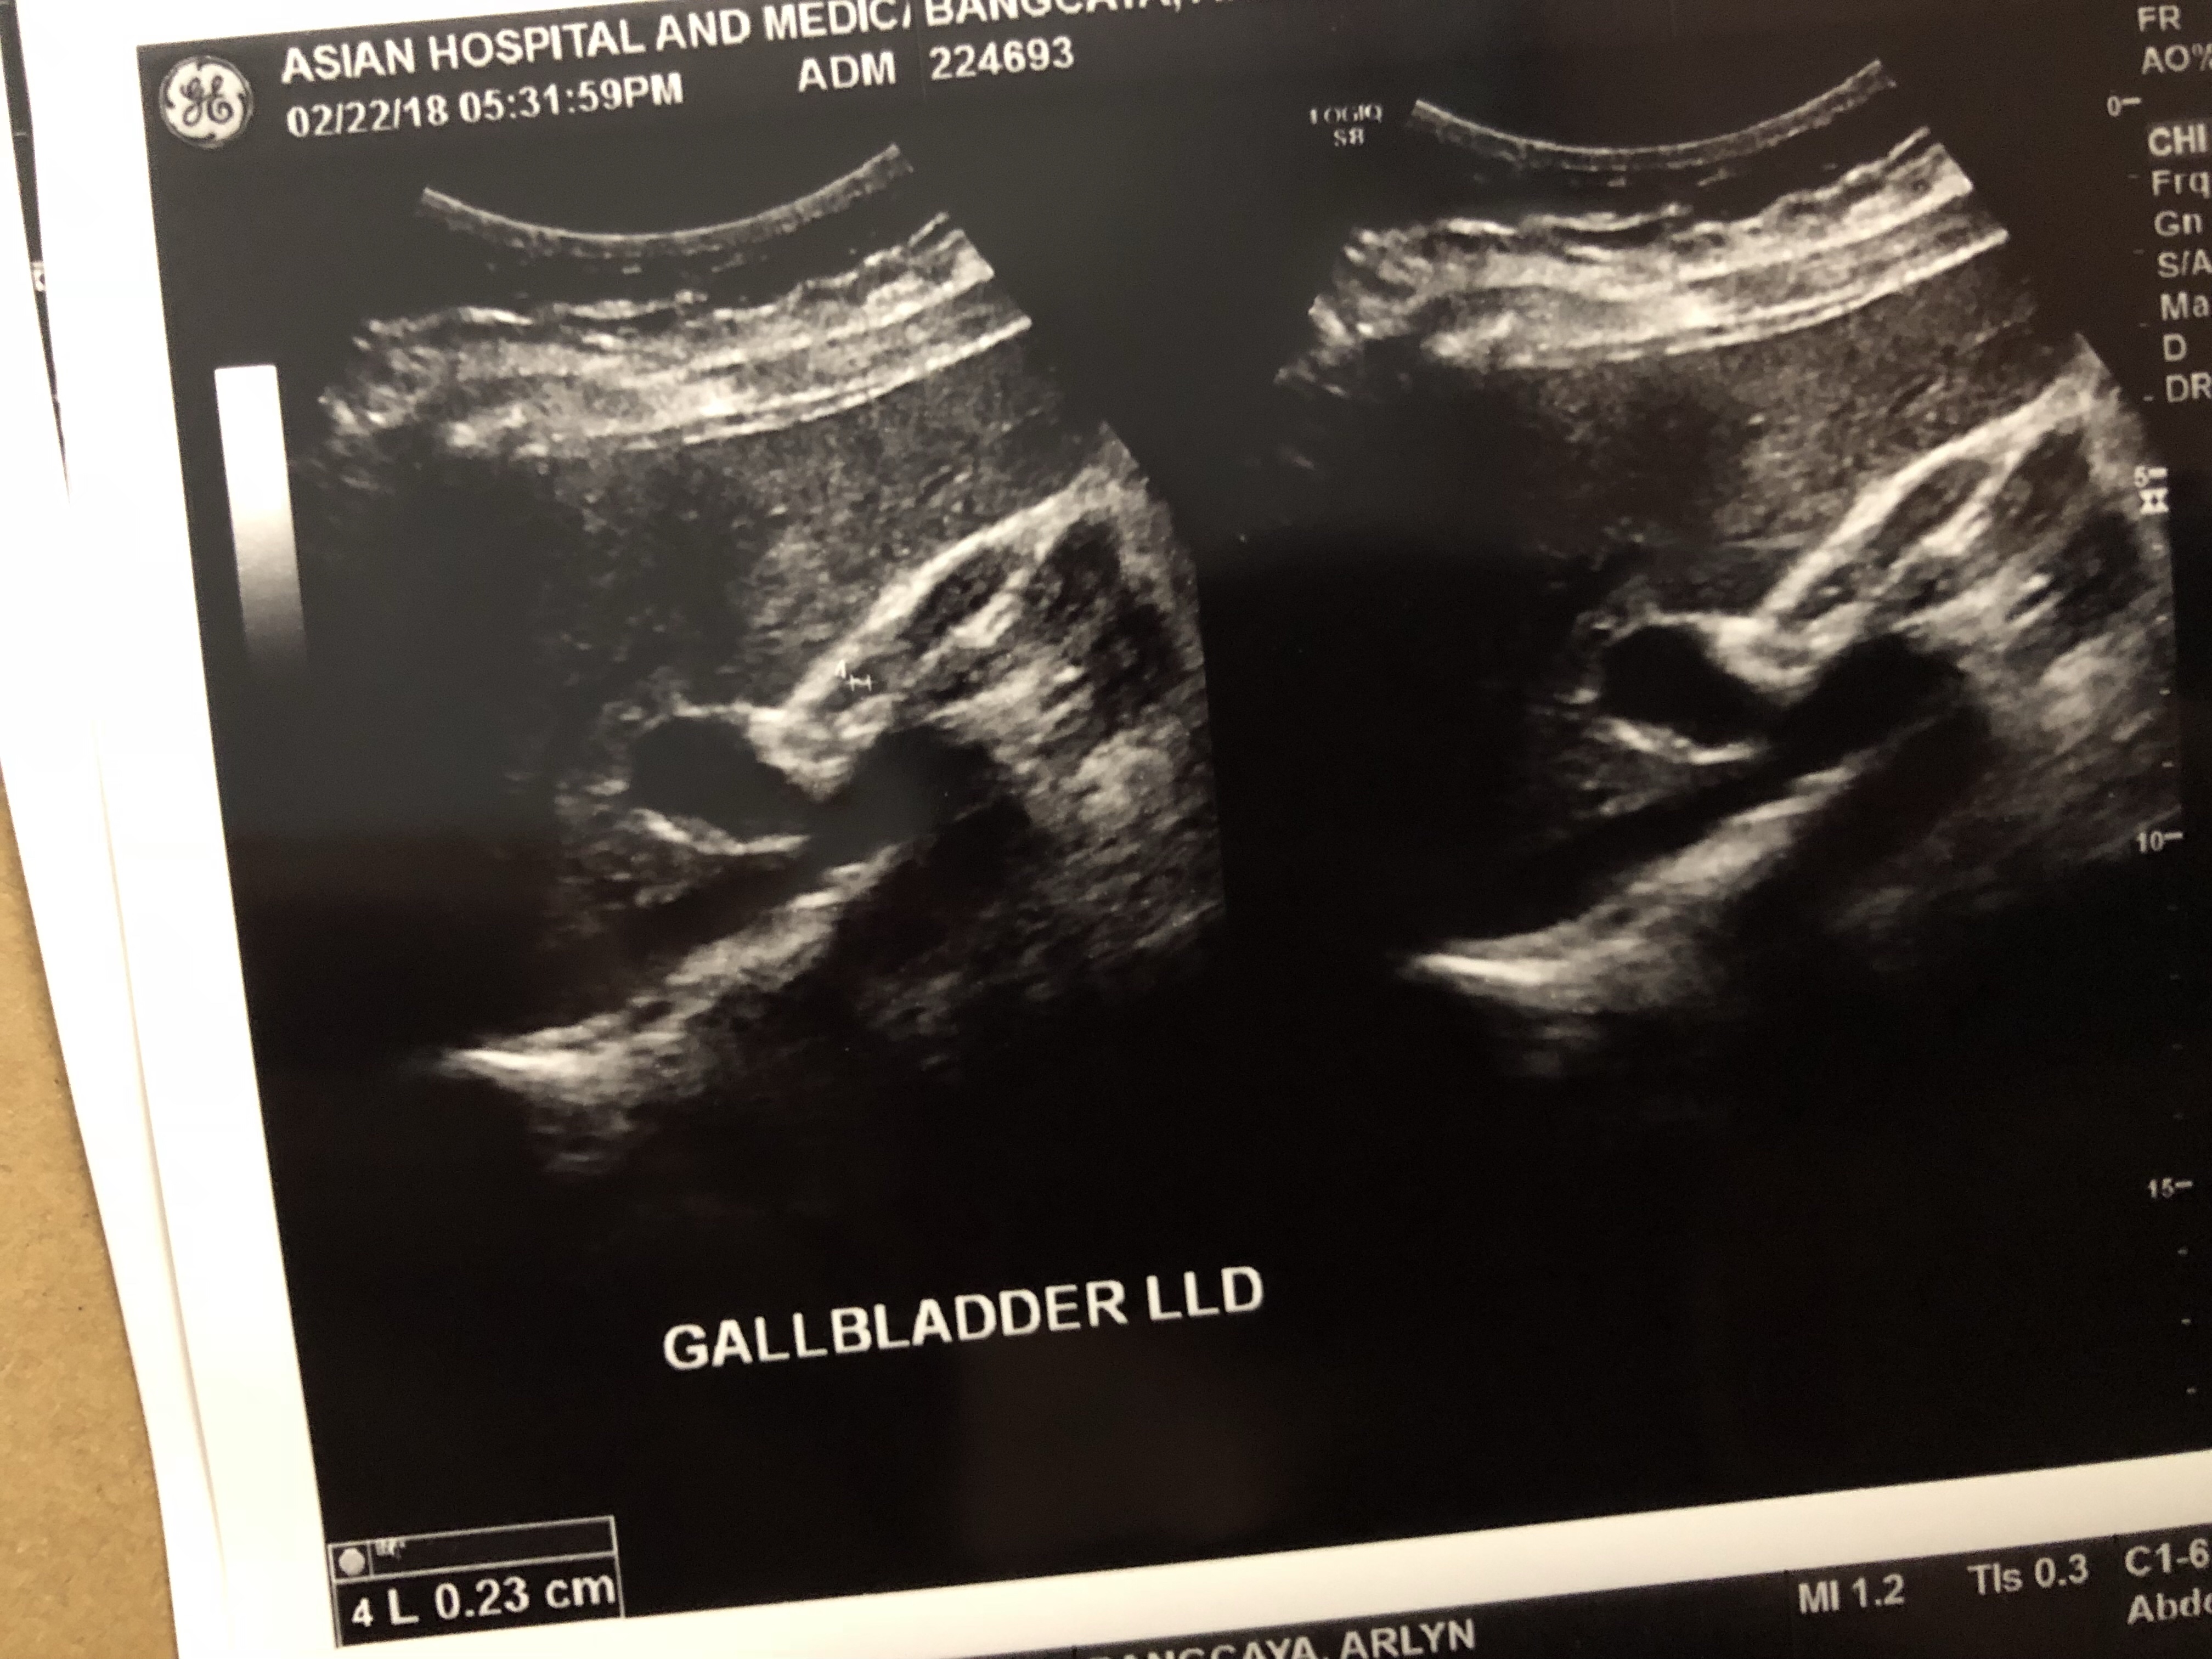

“You’ve lost weight? You look slim than the last time I saw you.” A friend remarked while we are eating snacks one hot afternoon. “You think so? I feel huge and my tummy is bulging.” Was my reply while complaining about the bloated feeling. “Well if you are feeling bad about it why don’t you … Continue reading LGBP Sonogram